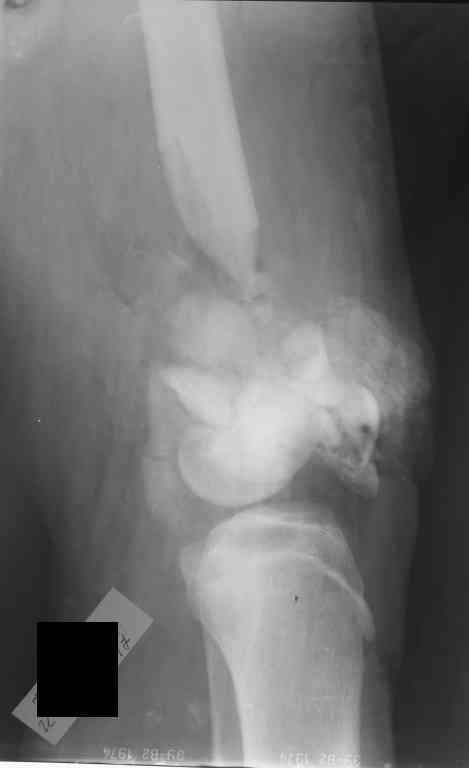

Внутрисуставной перелом бедренной кости

Уважаемые коллеги! Хотелось бы услышать ваше мнение по тактике лечения перелома бедра.

Пациент 17 лет. Травма 07.10.2006 - попал под грузовик. Рана на бедре зажила первичным натяжением. Мы рассматриваем следующие варианты: открытая репозиция + 1)остеосинтез аппаратом внешней фиксации; или 2)фиксация пластиной LCP. Ваши предложения? Как бы вы поступили с имеющимся дефектом бедренной кости?Екатерина Анатольевна Озерова

Глубокоуважаемая Екатерина Анатольевна !IMHO АВФ следовало бы поставить еще на этапе ПХО.При монтаже АВФ стоит предусмотреть возможность выращивания регенерата,а возможно,и модуль на коленный сустав для ранних движений.после выращивания регенерата можно,наверное,будет закрыто заштифтовать,но это вопрос будущего.Не совсем ясно,что там с надколенником.Хотелось бы уточнить,локальный статус на момент поступления и объем первичного вмешательства(в частности был ли вскрыт сустав)Ставить LCP на таком переломе,в условиях рубцов и при наличии дефекта-удовольствие еще то!

солидарен с коллегой в необходимости аппаратной фиксации на первом этапе. Спице-стержневой аппарат установленный на оба сегмента смог бы лигаментотаксисом подправить сусавные взаимоотношения. Минимально- инвазивный остеосинтез пластиной по латеральному контуру бедренной кости с введением коллапана в дефект, геля или гранул могут вполне закончиться консолидацией. А ревизию сустава, санацию хрящевой поверхности можно выполнить и позднее. Успехов Вам.

Картинка конечно страшненькая, но можно рискнуть и не открываться.

Внешняяя фиксация тем и хороша, что позволяет получать нормальные ФУНКЦИОНАЛЬНЫЕ результаты при жуткой анатомии. Попробуйте собрать закрыто. Адаптация возможна постепенная. Важно суставные поверхности сохранить конгруетными. постепенно загоните"шип" проксимального отломка в ценр мышелков и на фиксацию.